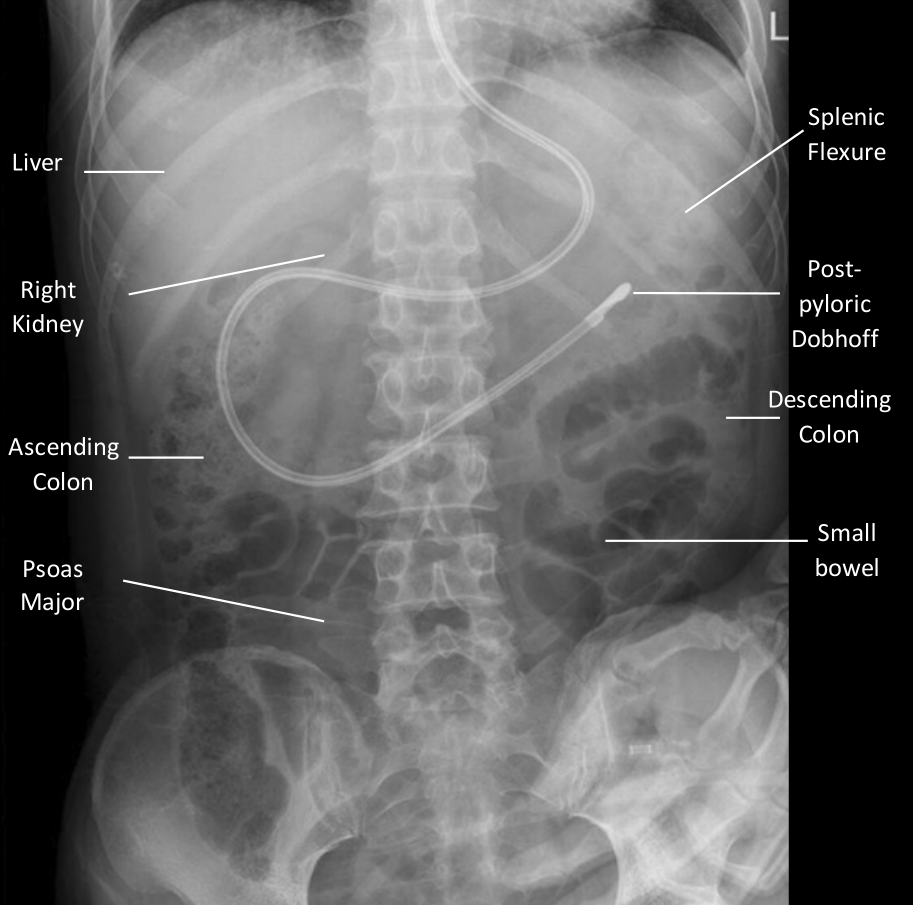

The nonobstructive bowel gas pattern appears as a normal arrangement of gas bubbles within the intestines. It shows that the intestines are functioning properly and that there are no blockages or abnormalities that could cause digestive issues.

In some cases, a nonobstructive bowel gas pattern may be seen in patients who are experiencing symptoms like bloating or abdominal pain. While this finding is reassuring, it’s essential for healthcare providers to consider other factors and conduct further tests if needed to determine the root cause of these symptoms.